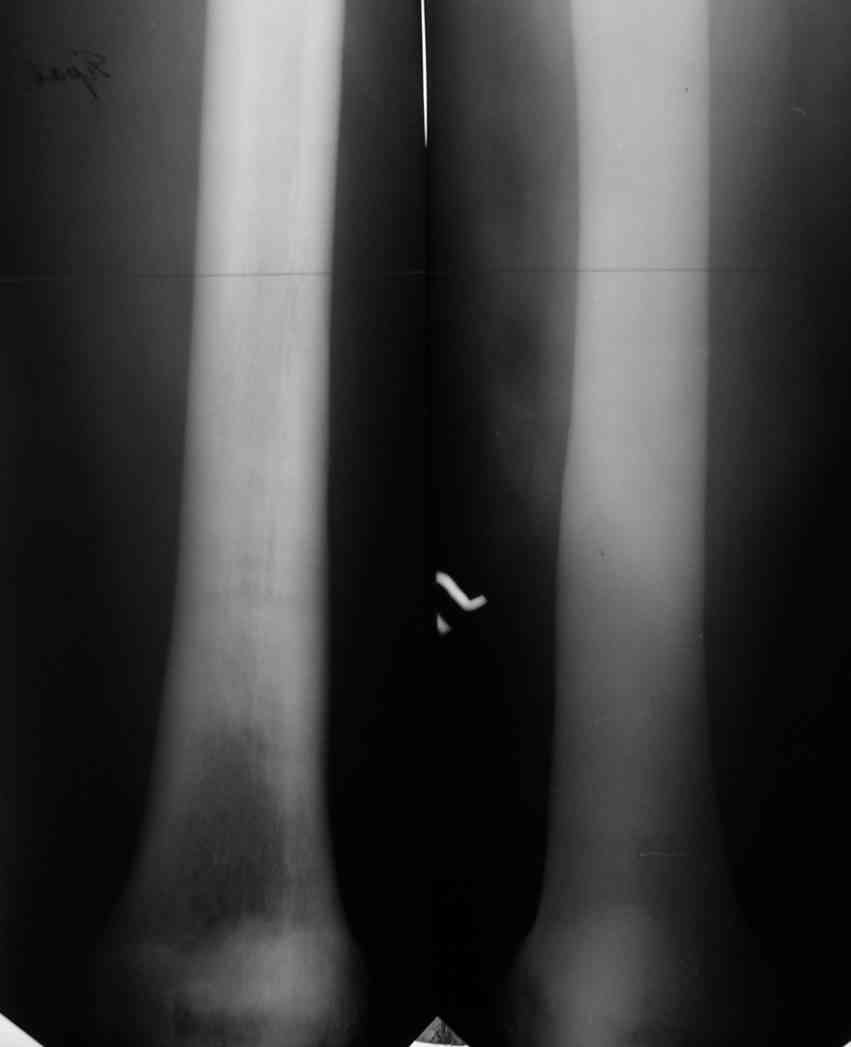

Изменения структуры костей у Вашего пациента больше похожи на полиоссальную форму фиброзной дисплазии или болезнь Педжета, возможены также инфаркты костного мозга б.берцовых костей. К сожалению, качество снимка не очень хорошее, непонятно, сохранен ли кортикальный слой б.берцовых костей по передней поверхности.

Для примера привожу случай из архива американской ассоциации рентгенологов (ACR) - развитие злокачественной фиброзной гистиоцитомы на левой б.берцовой кости у пациента с множественными инфарктами костного мозга (рис 4,5 - левая, рис 6 - правая)